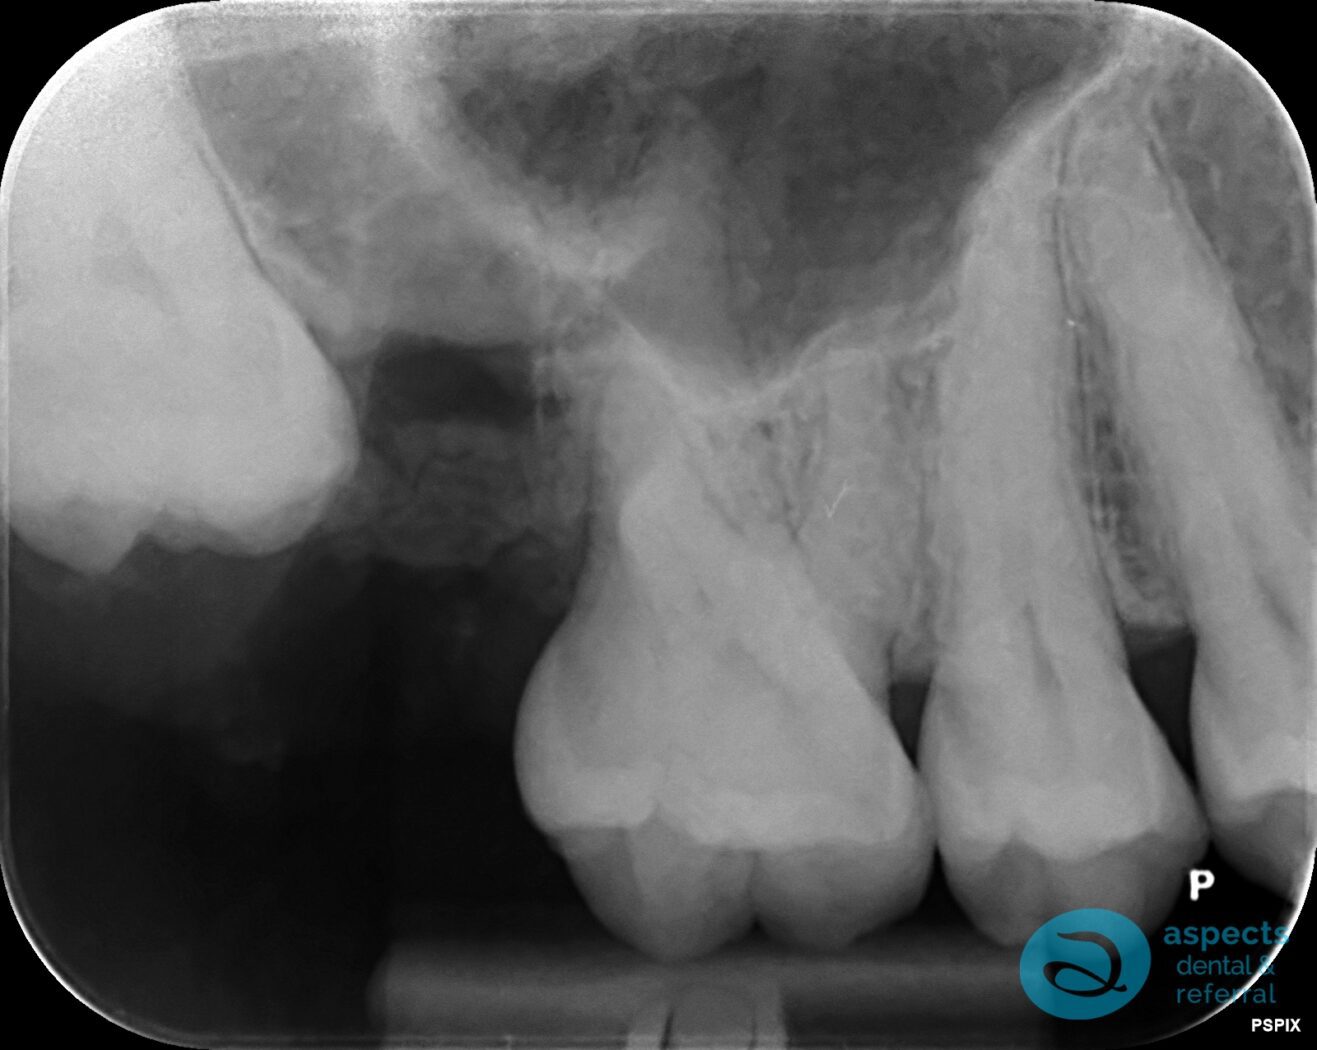

A minor surgical procedure was performed to remove the tooth using a minimally traumatic technique. All root apices were successfully retrieved intact, and care was taken to preserve the surrounding bone and soft tissues. The procedure was completed without complications.

After Surgical Tooth Extraction Xray